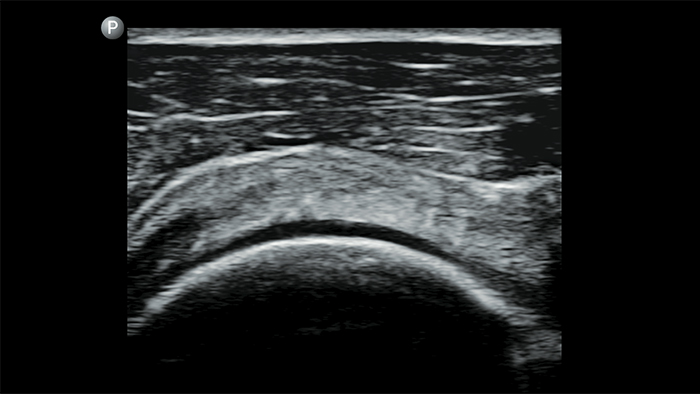

Breng echografie naar het bed

Het gebruik van Lumify aan het bed van uw patiënt kan een waardevol hulpmiddel zijn om de status van de maaginhoud te bepalen en kan hetrisico op pulmonale aspiratie verlagen. Samen kan dit het risico op anesthesiecomplicaties verminderen.